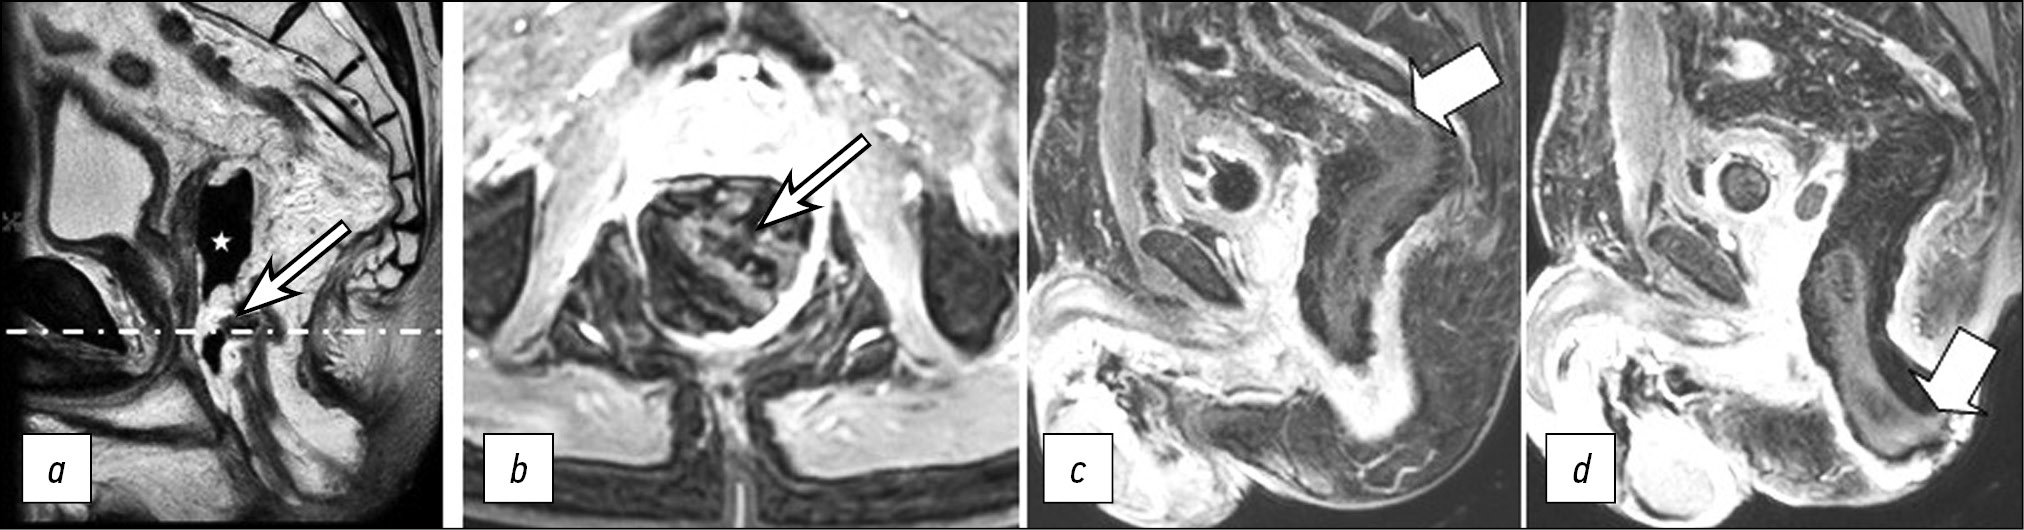

On the follow-up non-contrast-enhanced MRI, the previously detected changes (diffuse edema of the distal colon wall) were accompanied by a defect in the anterior wall of the coloplasty pouch, with a parietal air-filled cavity at the bottom in which a small amount of exudate was detected (Fig. 3). There were signs of necrosis in the pulled-through colon on rectoscopy (Fig. 4): the mucosa was violet-gray and dull; the lumen was deformed, and the folds were absent; the lumen contained blood and necrotic masses, and there was a putrid odor.

Figure 3. Pelvic MRI scans in Т2 mode on POD 6: two adjacent sagittal sections including the upper (a) and lower (b) segments of the pulled-through colon, with persistent diffuse edema of the walls; axial section (с) at the level of the dashed-dotted line. A defect in the anterior wall of the coloplasty pouch (arrow) with a parietal air-filled cavity (asterisk).

Fever up to 37.8℃ persisted on POD 10, but the CRP level decreased to 78.8 mg/L. A persistent defect in the wall of the coloplasty pouch with a parietal air-filled cavity was observed on a follow-up contrast-enhanced MRI; no contrast uptake was observed in the pulled-through colon segment (Fig. 5).

Figure 5. Pelvic MRI scans in Т2 mode (a) and 1-FS mode with contrast enhancement at the level of the dashed-dotted line in the axial plane (b) on POD 10: a defect in the wall of the coloplasty pouch (arrow) and an air-filled cavity (asterisk); two adjacent sagittal sections in 1-FS mode with contrast enhancement (c, d): the upper and lower edges of the ischemic colon segment (arrows).

Necrosis of the pulled-through colon segment, which necessitates emergency surgery, is an unfavorable outcome of acute ischemia. In our case, a follow-up MRI (POD 6) revealed diffuse edema in the pulled-through colon segment wall that persisted and an area of tissue destruction appeared. A defect containing fluid and gas formed in the wall of the coloplasty pouch. Changes in the MRI pattern were detected on POD 10 despite ongoing conservative therapy. A follow-up endoscopic examination confirmed the MRI findings of necrotic changes. Additionally, signs of a general inflammatory response increased, necessitating relaparotomy with disconnection of the anastomosis and resection of the necrotic portion of the colon.